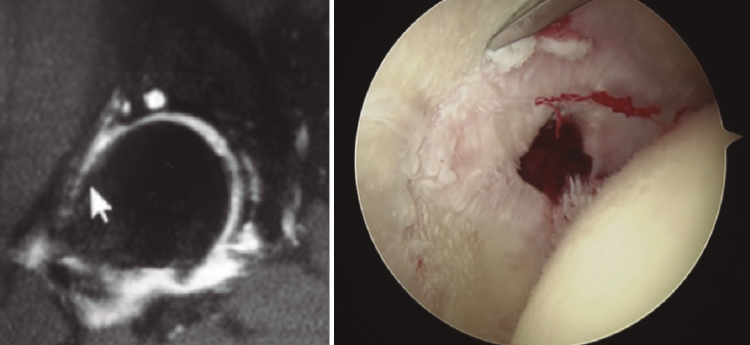

- El grupo de Berna(11)y el de la Mayo Clinic han descrito signos radiológicos cuya sola presencia aumenta la probabilidad de mal resultados en comparación con la ausencia de los mismos: a) osteofito en la fosa (multiplica por 3,2 veces la posibilidad de mal resultado); b) geodas subcondrales > 5 mm (multiplica por 4,1); y c) lesiones condrales de grado 3-4 que afecten al menos a 60° de la circunferencia acetabular (multiplica por 4,6). Además, los pacientes de CFA intervenidos con el hallazgo preoperatorio de estos 3 signos asocian un 0% de supervivencia a 6 años y los que tienen el a) y el c) un 20% a 6 años. De ahí que debamos buscar la presencia de estos y otros signos descritos en el artículo para informar a nuestro paciente de las posibilidades de éxito (Figura 1).

- Defectos capsulares: es importante en pacientes previamente intervenidos detectar en las artrorresonancias magnéticas (artro-RM) la existencia de defectos capsulares que, sumados a los previamente descritos, constituyen cada día con mayor claridad un criterio asociado a mala evolución clínica (Figura 2).

Figura 1. Paciente de 44 años con espacios < 2 mm en la zona 3, geodas subcondrales y osteofito de fosa. Pese a los factores en su contra, sus expectativas razonables nos inclinaron por la cirugía artroscópica. En la imagen de la derecha, resección del osteofito de fosa.

Figura 2. Paciente con geodas subcondrales acetabulares y en cabeza femoral, osteofito de contrachoque posteroinferior, espacios < 2 mm, incorrecta resección de CAM previo y defectos capsulares marcados.